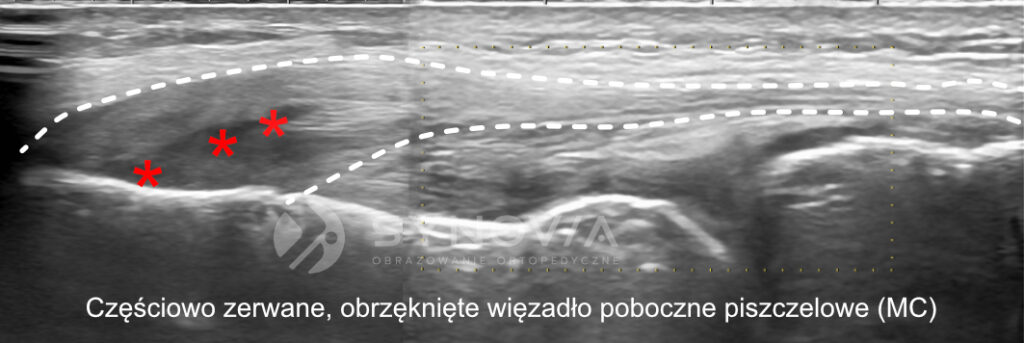

Więzadło poboczne przyśrodkowe (MCL) – ok. 4–5% wszystkich urazów

Drugie najczęstsze uszkodzenie kolana u narciarzy.

Powstaje w mechanizmie koślawienia – kolano zapada się do wewnątrz. Częsty scenariusz to kolizja z innym narciarzem albo niekontrolowane „rozjechanie się” nart.

Diagnostyka:

• USG – pełna ocena ciągłości MCL, widoczne włókna na całej długości

• ocena ognisk naderwań, obrzęku, płynu

• możliwość klasyfikacji uszkodzenia (I–III)